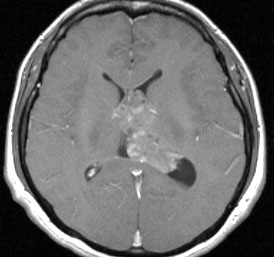

20代の男性の神経細胞腫です。側脳室の中のとても大きな腫瘍です。上段はガドリニウムという造影剤を入れた時のMRIです。下段の中央はCTですが,石灰化が見られます。脳外科の先生には,この脳室内腫瘍は一見transcallosal approach(経脳梁到達法)という手術で取れるように見えるかもしれませんが,そうではなくて,脳室の壁とくに上壁と側壁にくっついているのでなかなか取れません。この患者さんの場合は右の頭頂葉というところからtranscortical approach(経皮質到達法)で全摘出しました。後遺症もなく再発もなく術後10年が過ぎています。全部とれれば治ってしまう腫瘍です。